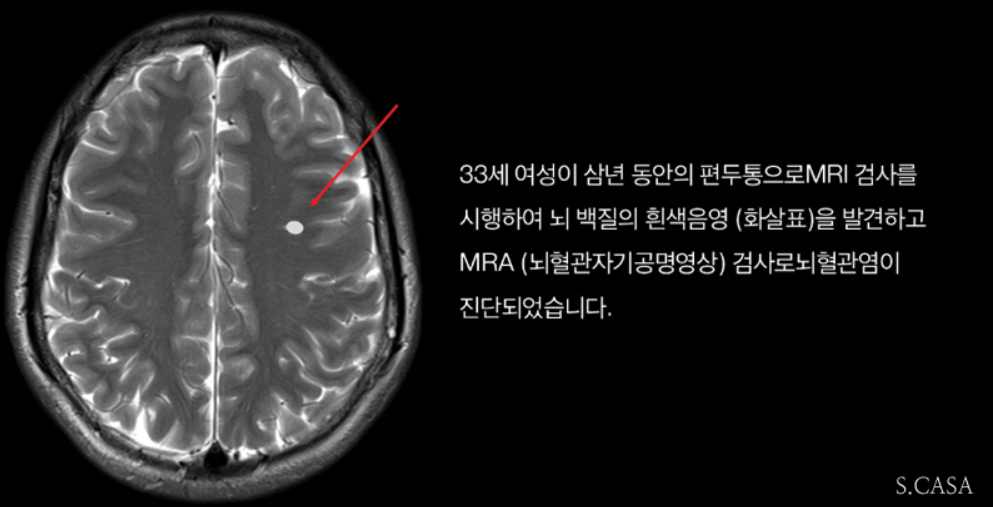

편두통과 유사한 다른 두통을 구분하기 위해서 뇌 컴퓨터 단층촬영(CT)이나 자기공명 영상(MRI)을 시행할 수도 있으며, 편두통의 기능적인 상태를 확인하기 위해 뇌 혈류 검사(TCD)를 시행하기도 합니다.